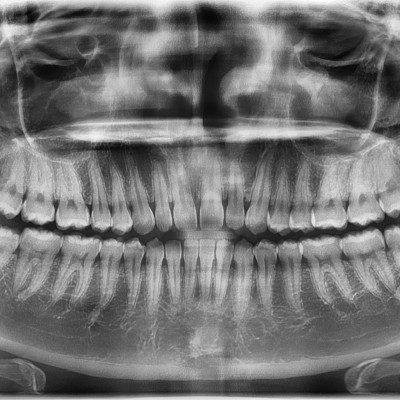

#18,28,38,48 사랑니 발치 #18,28,38,48 사랑니 발치 구강 외과 전문의가 당일 발치했습니다. ------------------..

작성자 이턱이 작성일 02-02 조회 6